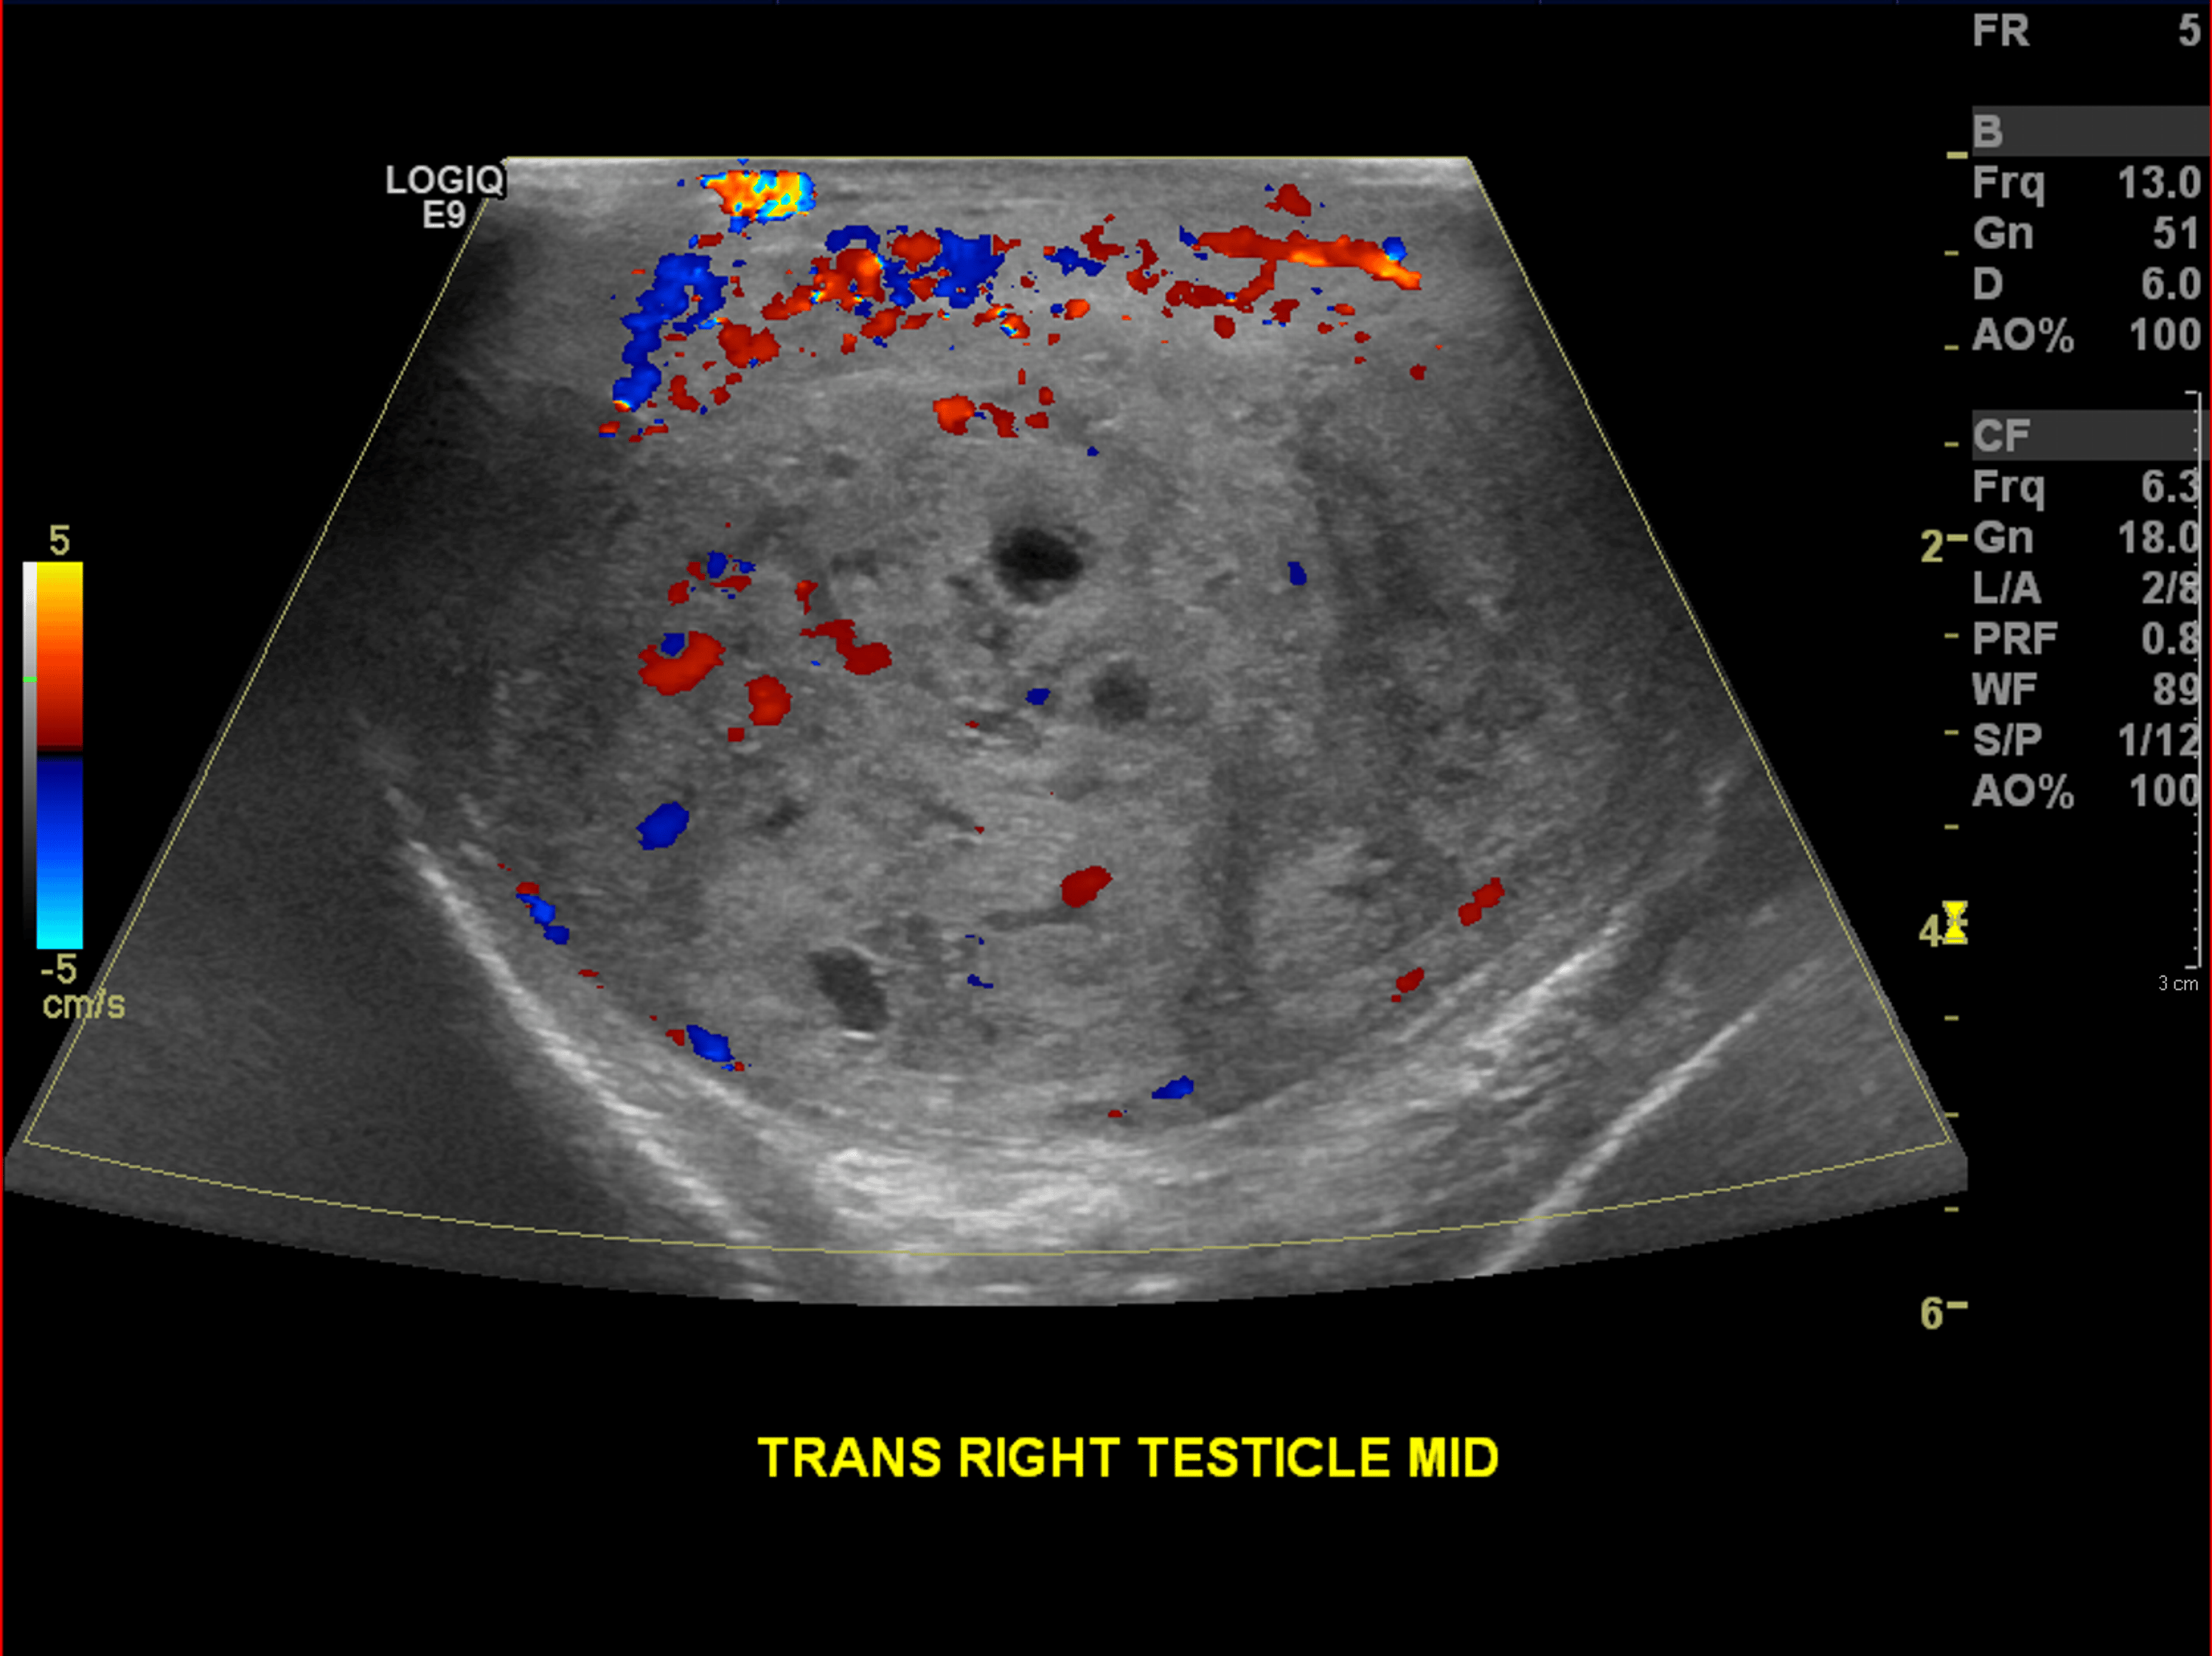

Cureus A Rare Case of Postorchidectomy Arterial Injury With Rapidly Enlarging Scrotal

From www.cureus.com

Cureus A Rare Case of Postorchidectomy Arterial Injury With Rapidly Enlarging Scrotal Coil Embolization Scrotum  It redirects blood away from an enlarged vein in your scrotum. During the procedure the doctor makes a small nick in the skin, (usually in the groin). It redirects blood away from an enlarged vein in your scrotum. Varicocele embolization is a type of medical procedure. Varicocele embolization is a type of medical procedure. Varicocele embolization is a minimally invasive. Coil Embolization Scrotum.

Cureus A Rare Case of Postorchidectomy Arterial Injury With Rapidly Enlarging Scrotal Coil Embolization Scrotum  There are several options for the treatment of varicocele, including surgical repair either by open or microsurgical approach, laparoscopy, or. Coils are commonly used embolic for varicocele, and both detachable and pushable. During the procedure the doctor makes a small nick in the skin, (usually in the groin). Varicocele embolization is an outpatient procedure with a short recovery time. It. Coil Embolization Scrotum.

Cureus A Rare Case of Postorchidectomy Arterial Injury With Rapidly Enlarging Scrotal Coil Embolization Scrotum  During the procedure the doctor makes a small nick in the skin, (usually in the groin). Varicocele embolization is a type of medical procedure. Varicocele embolization is a minimally invasive procedure which is used to treat abnormal enlargement and dysfunctional veins which. It redirects blood away from an enlarged vein in your scrotum. Varicocele embolization is an outpatient procedure with. Coil Embolization Scrotum.

Cureus A Rare Case of Postorchidectomy Arterial Injury With Rapidly Enlarging Scrotal Coil Embolization Scrotum  It redirects blood away from an enlarged vein in your scrotum. During the procedure the doctor makes a small nick in the skin, (usually in the groin). Coils are commonly used embolic for varicocele, and both detachable and pushable. It redirects blood away from an enlarged vein in your scrotum. There are several options for the treatment of varicocele, including. Coil Embolization Scrotum.

Cureus A Rare Case of Postorchidectomy Arterial Injury With Rapidly Enlarging Scrotal Coil Embolization Scrotum  Varicocele embolization is a type of medical procedure. It redirects blood away from an enlarged vein in your scrotum. Varicocele embolization is an outpatient procedure with a short recovery time. Coils are commonly used embolic for varicocele, and both detachable and pushable. It redirects blood away from an enlarged vein in your scrotum. During the procedure the doctor makes a. Coil Embolization Scrotum.

Cureus A Rare Case of Postorchidectomy Arterial Injury With Rapidly Enlarging Scrotal Coil Embolization Scrotum  During the procedure the doctor makes a small nick in the skin, (usually in the groin). Varicocele embolization is a type of medical procedure. It redirects blood away from an enlarged vein in your scrotum. Varicocele embolization is a minimally invasive procedure which is used to treat abnormal enlargement and dysfunctional veins which. There are several options for the treatment. Coil Embolization Scrotum.

Cureus A Rare Case of Postorchidectomy Arterial Injury With Rapidly Enlarging Scrotal Coil Embolization Scrotum  Varicocele embolization is a minimally invasive procedure which is used to treat abnormal enlargement and dysfunctional veins which. Coils are commonly used embolic for varicocele, and both detachable and pushable. There are several options for the treatment of varicocele, including surgical repair either by open or microsurgical approach, laparoscopy, or. During the procedure the doctor makes a small nick in. Coil Embolization Scrotum.

Cureus A Rare Case of Postorchidectomy Arterial Injury With Rapidly Enlarging Scrotal Coil Embolization Scrotum  Varicocele embolization is an outpatient procedure with a short recovery time. Coils are commonly used embolic for varicocele, and both detachable and pushable. There are several options for the treatment of varicocele, including surgical repair either by open or microsurgical approach, laparoscopy, or. During the procedure the doctor makes a small nick in the skin, (usually in the groin). It. Coil Embolization Scrotum.